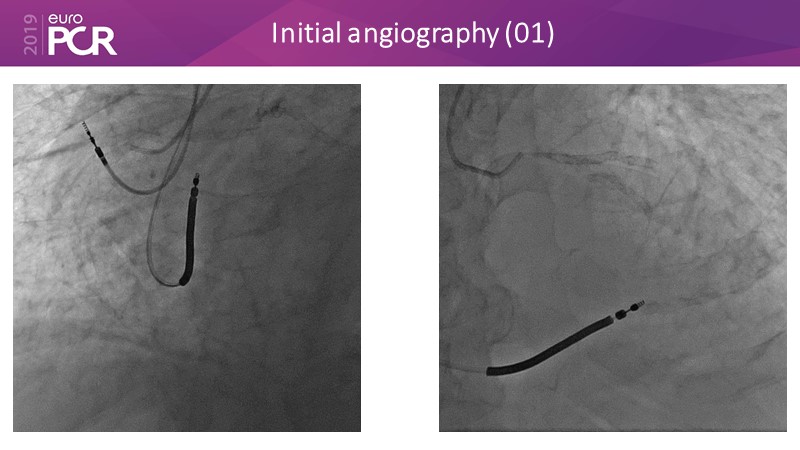

Distal left main stenosis: how to treat optimally with dedicated bifurcation stent BiOSS Lim C. Case-based session